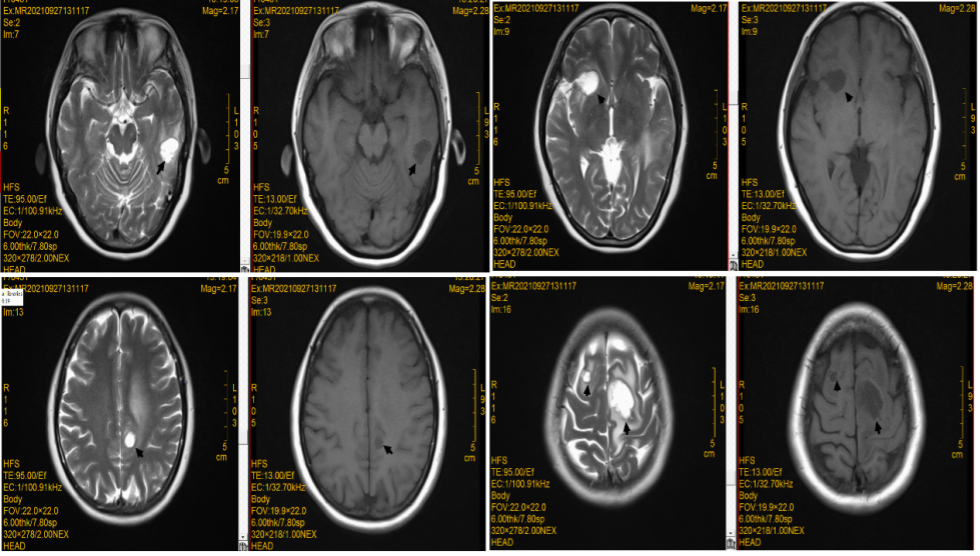

脑转移病灶:一线阿美替尼联合化疗治疗颅内病灶,第二次疗效评估即治疗5个月(20220308)后疗效评价为PR,治疗12个月后(20221011)患者脑转移病灶疗效仍为PR。

图5:治疗5个月颅脑MRI检查

图6:治疗约12个月颅脑MRI检查

1. 该病例是一个肺腺癌(T2bN1M1c)IVB期患者,初诊时已有颅脑多发转移、骨转移,且患有乙肝,基因检测为EGFR 19del阳性。一线治疗采用卡铂+培美曲塞4周期+阿美替尼110mg qd+唑来膦酸治疗,已经持续用药超14个月。治疗6周后肺部病灶疗效评价即为PR,治疗5个月后脑部病灶同样PR,骨转移异常浓度较之前减少,原发病灶和转移病灶均得到控制。更重要的是安全性佳,患者病情稳定,未出现严重的不良反应。虽然出现了转氨酶轻度升高,但处理后快速下降至正常值。